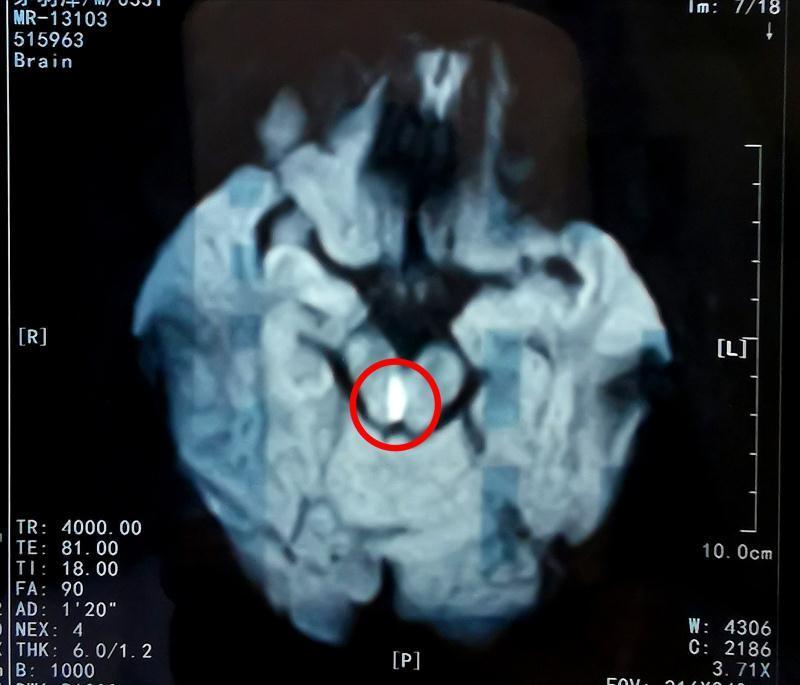

Lúc này, anh đột nhiên thấy choáng váng, mắt mờ không nhìn rõ chữ. Ngay lập tức, bệnh nhân nhờ gia đình đưa mình tới bệnh viện. Qua kiểm tra ban đầu, bác sĩ tiến hành chụp cộng hưởng MRI và xác định bệnh nhân bị nhồi máu não. Chẩn đoán này khiến gia đình anh không tin, một chàng trai khoẻ mạnh tuổi 30, không có tiền sử bệnh tật làm sao có thể bị nhồi máu não được.

Sau đó, Tiểu Trương được chuyển đến Bệnh viện Đại học Khoa học và Công nghệ Quốc gia, và trung tâm đột quỵ đã tiến hành kiểm tra toàn diện. Bác sĩ nhận thấy các mạch máu lớn của bệnh nhân vẫn trong tình trạng tốt, nhưng nhồi máu não bị gây ra bởi sự tắc động mạch máu nhỏ.

Do vị trí cục máu đông nên nó gây tổn thương cho trung tâm chỉ huy chuyển động mắt. Điều này khiến cho một nhãn cầu của anh bị hạn chế cử động, nhãn cầu còn lại thì hoạt động bình thường.